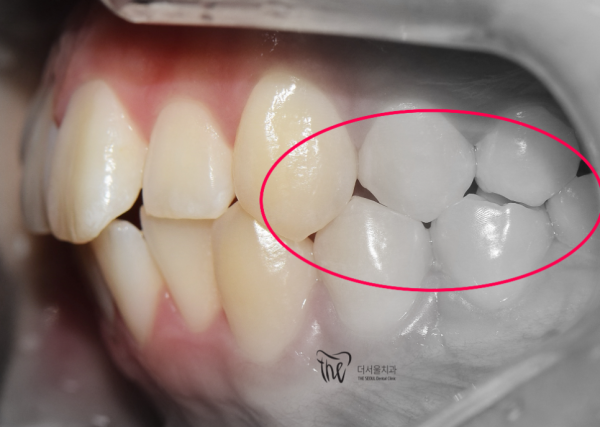

하지만 좌측의 치아를 보면, 어금니가 반대교합을 보이고 있습니다.

(맨 위의 사진과 비교해보면 위쪽 어금니가 다르게 교학되는 것을 확인할 수 있으세요)

거꾸로 물리는 반대교합에 의해 턱관절의 통증까지 느끼고 계셨습니다.

이 환자분은 교정과 턱관절의 치료라는 두가지 목적으로 태평역 더서울치과를 찾아주셨습니다.

But if you look at the teeth on the left, the molars are showing the opposite occlusion.

(Compared to the picture at the top, you can see that the upper molars are taught differently.)

He was even feeling pain in the jaw joint due to the reverse occlusion of the bite.

This patient visited The Seoul Dental Clinic in Taepyeong Station for two purposes: correction and treatment of the jaw joint.